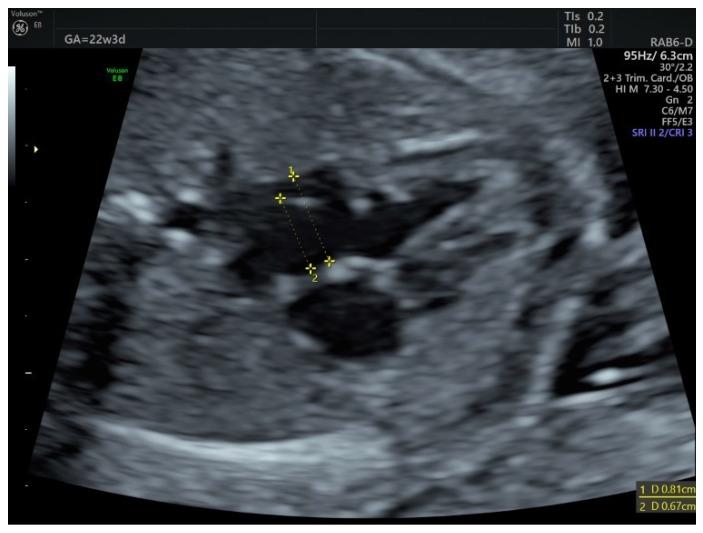

胎儿房间隔瘤:孕中期至孕晚期的随访

Fetal Atrial Septal Aneurysm: Follow-Up from Second to Third Trimester.

Atrial septal aneurysm (ASA) is a rarely reported fetal finding. Its definition is variable, but the diagnosis is usually made when the foramen ovale flap extends at least halfway across the left atrium. It is considered a transient, self-limiting condition, but on occasion, it can be complicated by fetal arrhythmia or left ventricular (LV) inflow obstruction-if longstanding, this can lead to left heart hypoplasia. We present two cases of ASA diagnosed at the second trimester scan, one of which was subsequently complicated by LV inflow obstruction and prenatal suspicion of hypoplastic aortic arch. This report is a good illustration of how structure follows function: a small LV preload can lead to a decreased LV output, which in turn will end up in a hypoplastic LV and outflow tract-all this is reversible after birth, due to the physiological circulatory modifications that occur in the newborn.

摘要

房间隔瘤(ASA)是一种报道较少的胎儿检查结果。其定义存在差异,但通常在卵圆孔瓣延伸至左心房至少一半时作出诊断。它被认为是一种短暂的、自限性疾病,但偶尔会并发胎儿心律失常或左心室(LV)流入道梗阻——如果长期存在,可能导致左心发育不全。我们报告两例在孕中期超声检查时诊断出的ASA病例,其中一例随后并发LV流入道梗阻,并在产前怀疑主动脉弓发育不全。本报告很好地说明了结构如何随功能变化:左心室前负荷小会导致左心室输出量减少,进而导致左心室和流出道发育不全——由于新生儿发生的生理性循环改变,所有这些在出生后都是可逆的。